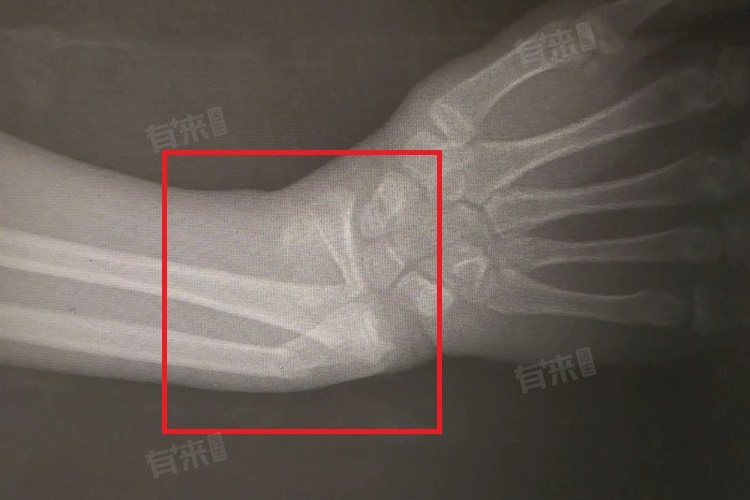

- 诊断10岁小孩右桡骨远端骨折,医生首先进行详细的体格检查,观察受伤部位有无肿胀、畸形,触诊判断疼痛位置和程度,检查手腕活动功能。X线检查是确诊的关键,通过拍摄右前臂正侧位X线片,可清晰显示桡骨远端骨折的类型、骨折线走向、骨折端移位情况等,为治疗方案的制定提供重要依据。若X线检查难以明确骨折细节,或怀疑合并有骺板损伤、细微骨折等情况,会进一步进行CT检查,CT的三维重建图像能更直观、准确地显示骨折情况。